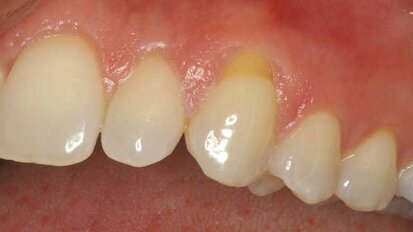

Barriers of success: Cosmetic periodontal surgery (Part 4B)

This is a continuation of the fourth article in a series of Dental Tribune clinical articles dealing with cosmetic periodontal surgery. As a follow-up to ...